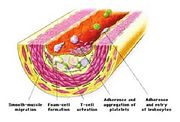

| 00:09, 15 October 2006 | Muscle.jpg (file) |  |

55 KB | 1 | ||